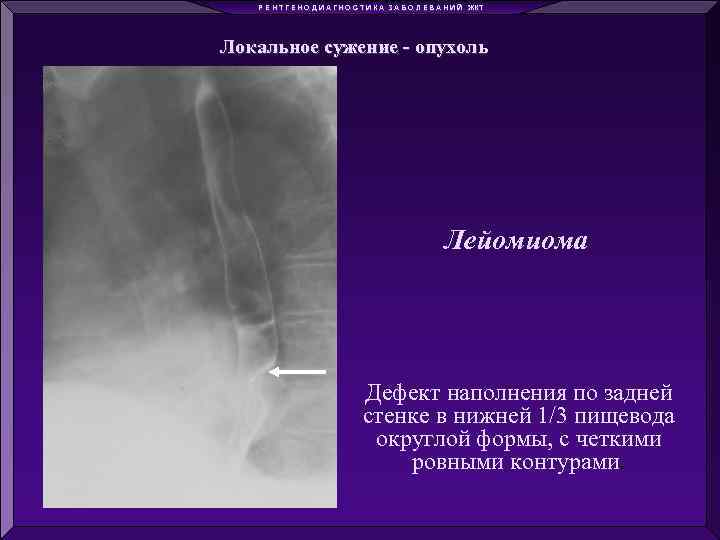

Р Е Н Т Г Е Н О Д И А Г Н О С Т И К А З А Б О Л Е В А Н И Й ЖКТ Диффузное сужение - ожог Локальное сужение - опухоль Диффузное расширение – ахалазия кардии Локальное расширение - дивертикулы

Р Е Н Т Г Е Н О Д И А Г Н О С Т И К А З А Б О Л Е В А Н И Й ЖКТ Диффузное сужение - ожог Локальное сужение - опухоль Диффузное расширение – ахалазия кардии Локальное расширение - дивертикулы

Р Е Н Т Г Е Н О Д И А Г Н О С Т И К А З А Б О Л Е В А Н И Й ЖКТ Локальное сужение - опухоль Лейомиома Дефект наполнения по задней стенке в нижней 1/3 пищевода округлой формы, с четкими ровными контурами.

Р Е Н Т Г Е Н О Д И А Г Н О С Т И К А З А Б О Л Е В А Н И Й ЖКТ Локальное сужение - опухоль Лейомиома Дефект наполнения по задней стенке в нижней 1/3 пищевода округлой формы, с четкими ровными контурами.